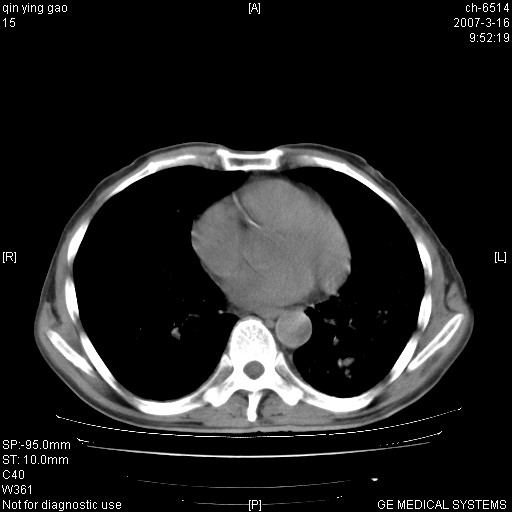

男,64岁.乏力2个月,畏寒、发热1月余。体重下降。血沉加快,白细胞不高。

双肺以中上肺野为著斑片状.结节壮密度增高影 左上肺前段可见小类圆钙化灶 纵隔淋巴结无明显肿大

3.主动脉弓.冠状动脉钙化形成

双肺以中上肺野为著斑片状.结节壮密度增高影,纵隔淋巴结无明显肿大。考虑:

1、肺结核。

2、主动脉、冠状动脉硬化。

病变以两肺上野为著,部分病灶有钙化,纵隔窗显示病灶有新老不一,这个首先和结核脱不了干系,还有部分病灶有融洽的倾向,肿瘤也不能完全排出